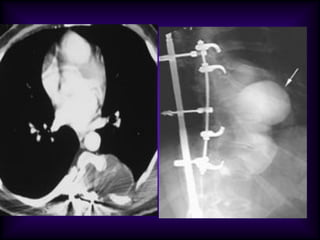

Achalasia of

esophagus

• Inhomogeneous

cardiac density:

Right half more

dense than left

• Density crossing

midline (right black

arrow)

• Right sided inlet to

outlet shadow

• Right para spinal line

(left black arrow)

• Barium swallow

below: Dilated